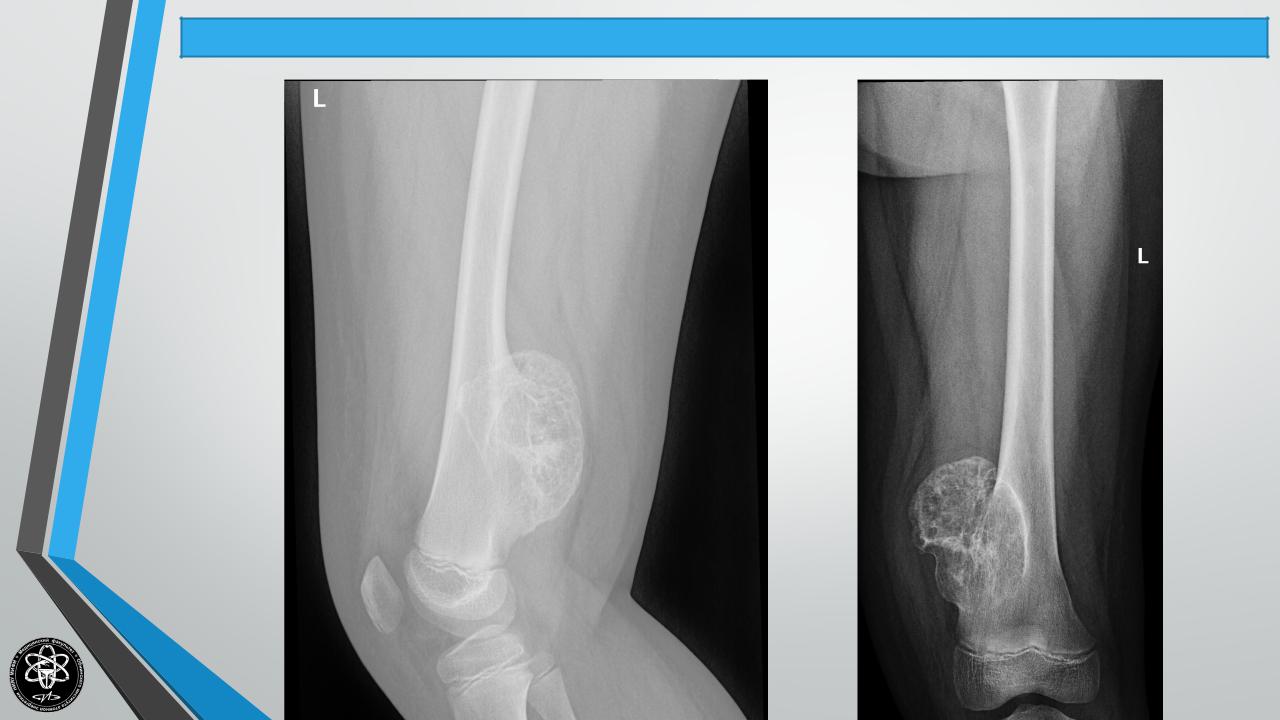

Остеобластокластома(костнаякиста,гигантоклеточнаяопухоль, аневризмакости)

Рентгенологически

остеолитическая

или

остеопластическая формы, “Козырек”, “спикулы”. Лабораторные сдвиги — СОЭ нарастает до 30-50 и

более

мм/час,

растет

щелочная

фосфатаза.